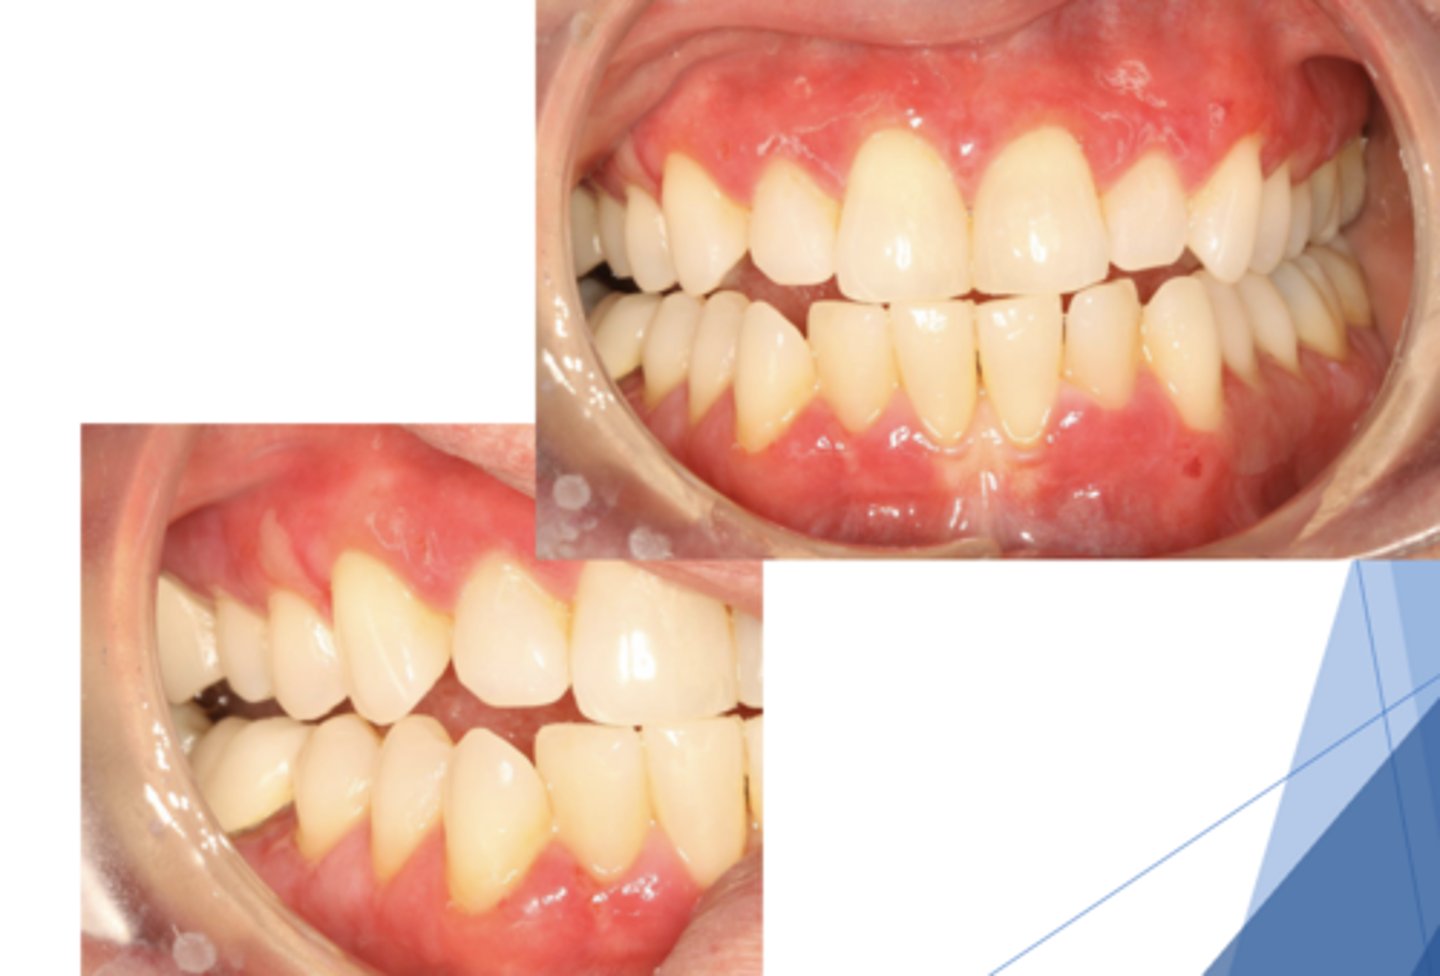

lichen planus (erosive/erythematous)

What type of lichen planus?

- Often symptomatic

- Striae at periphery of erythema

- May cause desquamative gingivitis

- Must be distinguished from mucous membrane pemphigoid or pemphigus

What condition?

lichen planus (ulcerative)

- Least common form

- Usually symptomatic

- Ulcers w/ striae + erythema

lichen planus (ulcerative and some reticular and erythematous seen)